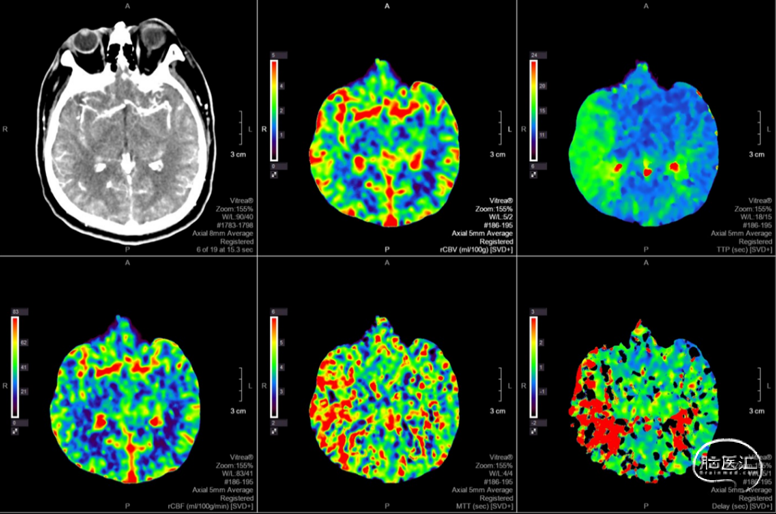

头颅CTP:右侧大脑中动脉区域明显低灌。